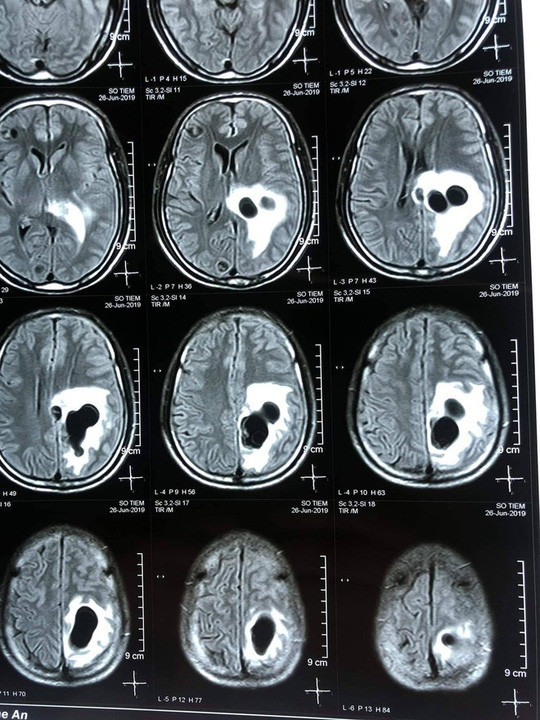

| Não nạn nhân có nhiều sán làm tổ do ăn tiết canh. |

Qua thăm khám và chụp CT não, các bác sĩ phát hiện có 5 ổ sán nằm rải rác trong não ông S., trong đó có một ổ sán lớn trên đỉnh não của bệnh nhân gây phù não.